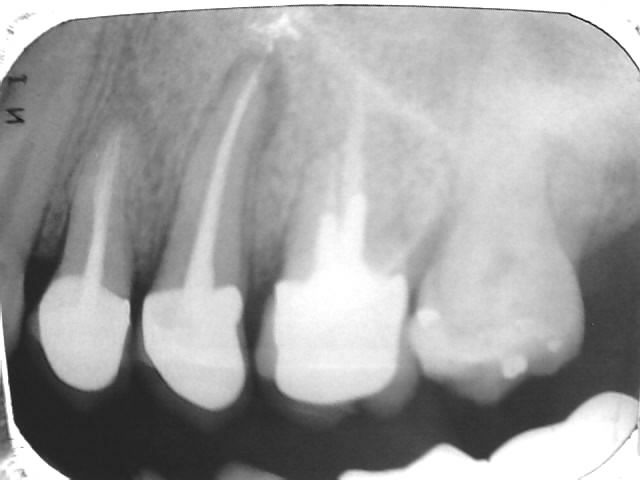

Le diagnostic radiologique des fêlures radiculaires dentaires est très difficile à faire, même pour les radiologues.

Je ne connais qu’un seul moyen de détecter une fêlure, c’est l’aspect radiologique de la lésion osseuse correspondante.

Cette lésion péri-radiculaire est dite « lésion en chaussette » et permet de faire le diagnostic certain d’une fêlure.

Il est bien évident, que l’apparition de nouvelles techniques d’imagerie telles que cône beam, 3D, Dentascan, ou scanner améliorent considérablement les possibilités de diagnostic des fêlures radiculaires. Mais la fêlure en elle même reste rarement visible, c’est l’aspect de la lyse osseuse engendrée par l’infiltration bactérienne ,qui reste déterminante pour le diagnostic.